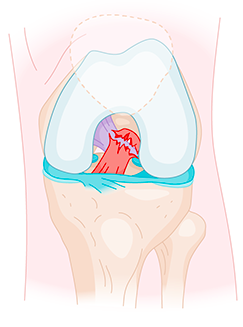

Le ligament croisé antérieur (LCA) est un ligament qui se situe au centre du genou. Son rôle est de stabiliser le genou. Il joue un rôle très important dans les sports de pivot (football, hockey, basket, rugby,etc). Sans ligament, il existe de réels risques d’entorses à répétition lors de la pratique sportive. Ces entorses entrainent à terme des lésions des ménisques et du cartilage favorisant le développement de l’arthrose à terme. Par sa vascularisation particulière et son anatomie, une fois rompu, il ne guérit pas spontanément.

Le principe de cette intervention est de reconstruire le ligament à son emplacement anatomique exact, en utilisant un ou deux tendons prélevés sur l’opéré lui-même (autogreffe). Ce nouveau ligament est mis en place dans l’articulation par l’intermédiaire de deux petits tunnels osseux, au niveau du tibia et du fémur. Cette intervention se fait par arthroscopie (caméra et 2 petits orifices de 1 cm).

Les tunnels permettent de faire passer la greffe à l’intérieur de l’articulation, pour la placer à l'endroit où était situé l’ancien ligament croisé antérieur. Il y a donc un tunnel tibial et un tunnel fémoral.